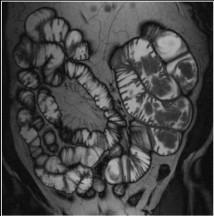

Polyp hamartomateux de

l'intestin : Image IRM T2 en coronal . Aspect

des masse polypoide hypo-signal etendue le long de

l'intestin |